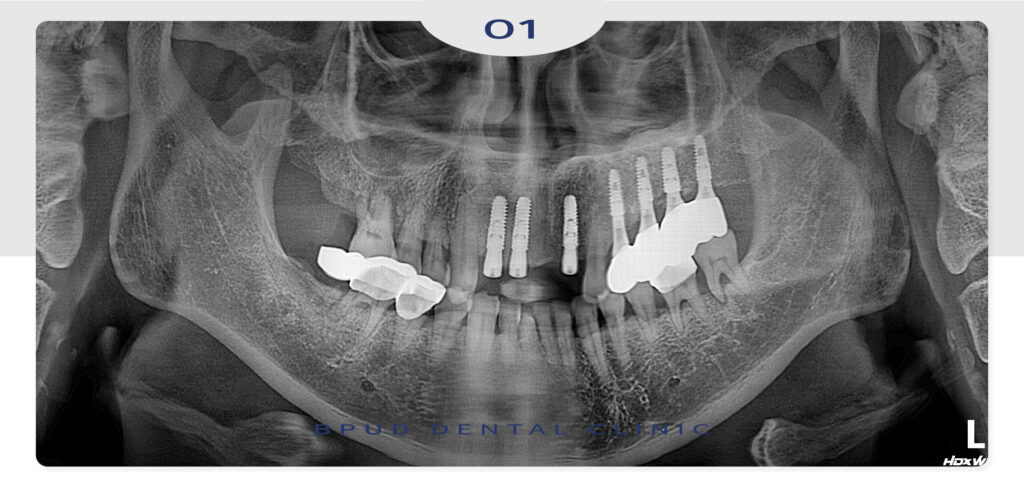

길지 않은 치료 기간 내에

어려운 케이스를 모두 마무리하여

환자분께서도 매우 만족하셨는데요.

나머지 좋지 않은 치아들도 순차적으로

임플란트 진행 계획을 수립하였답니다~

수술 후에는 감염 예방과 이식된 뼈의 안정적

장착을 위해 정기 검진과 철저한 위생 관리가

요구되는데요.

회복 상태를 지속적으로 확인하고 필요 시

신속히 대응하는 사후 관리 과정 역시

성공적인 치료에 중요한 요소입니다.